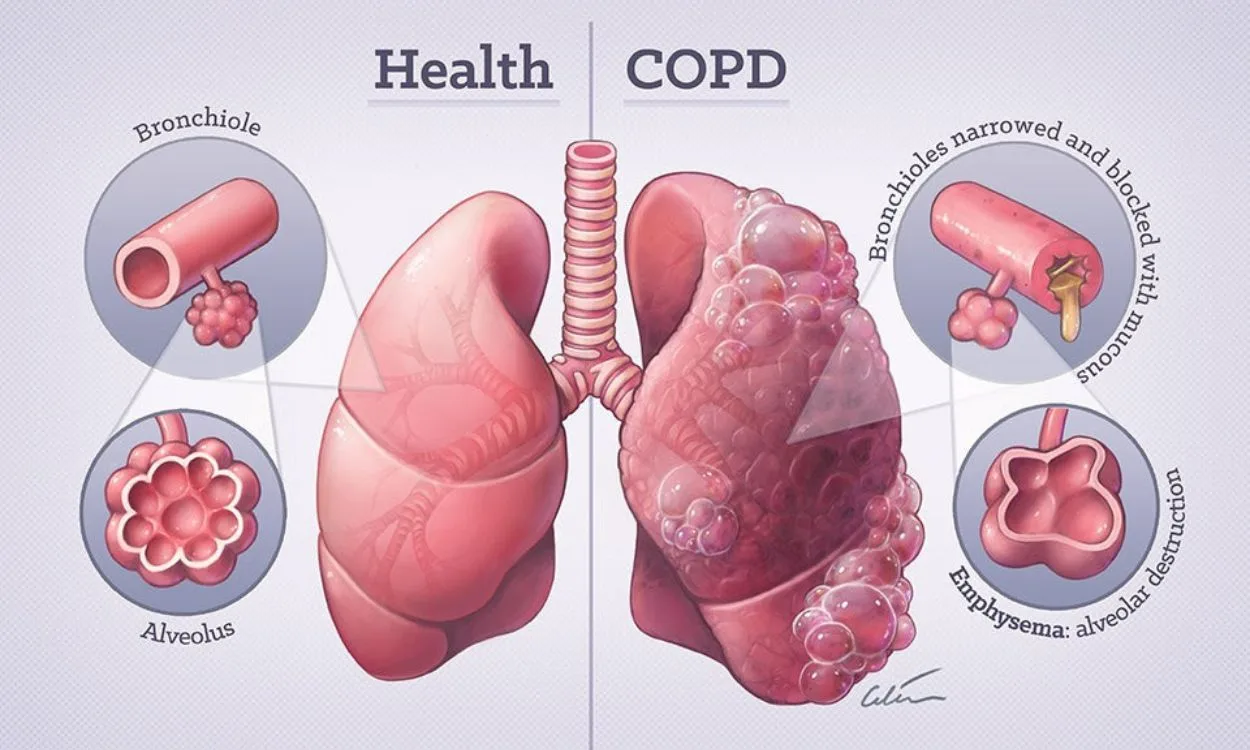

- Lung disease(52)

- Lung Health(52)